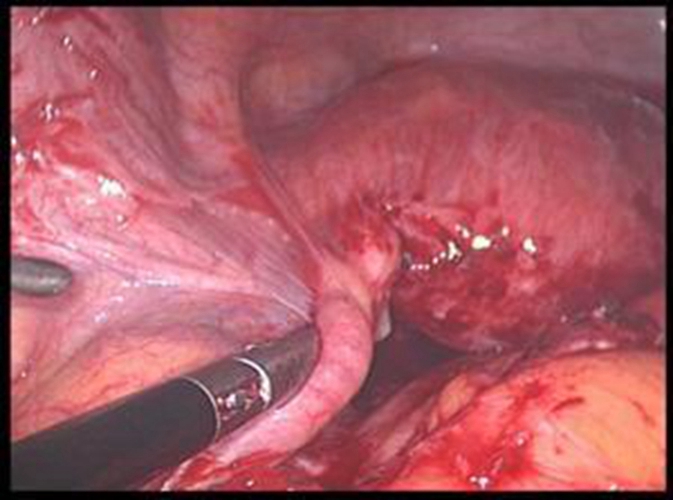

巧克力囊腫圖片

輸卵管巧克力囊腫

輸卵管巧克力囊腫排出

輸卵管囊腫手術